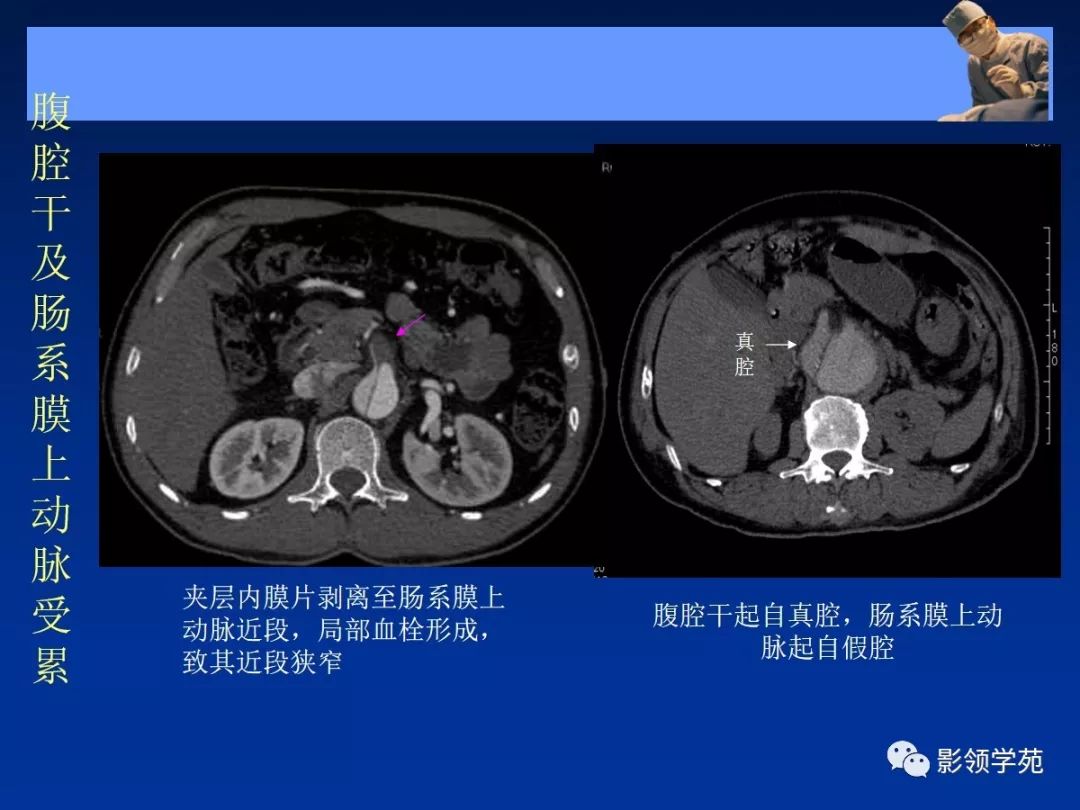

- 主动脉夹层(aortic dissection, AD)

- 真假“双腔” ,存在交通

- 远段同时存在再破口